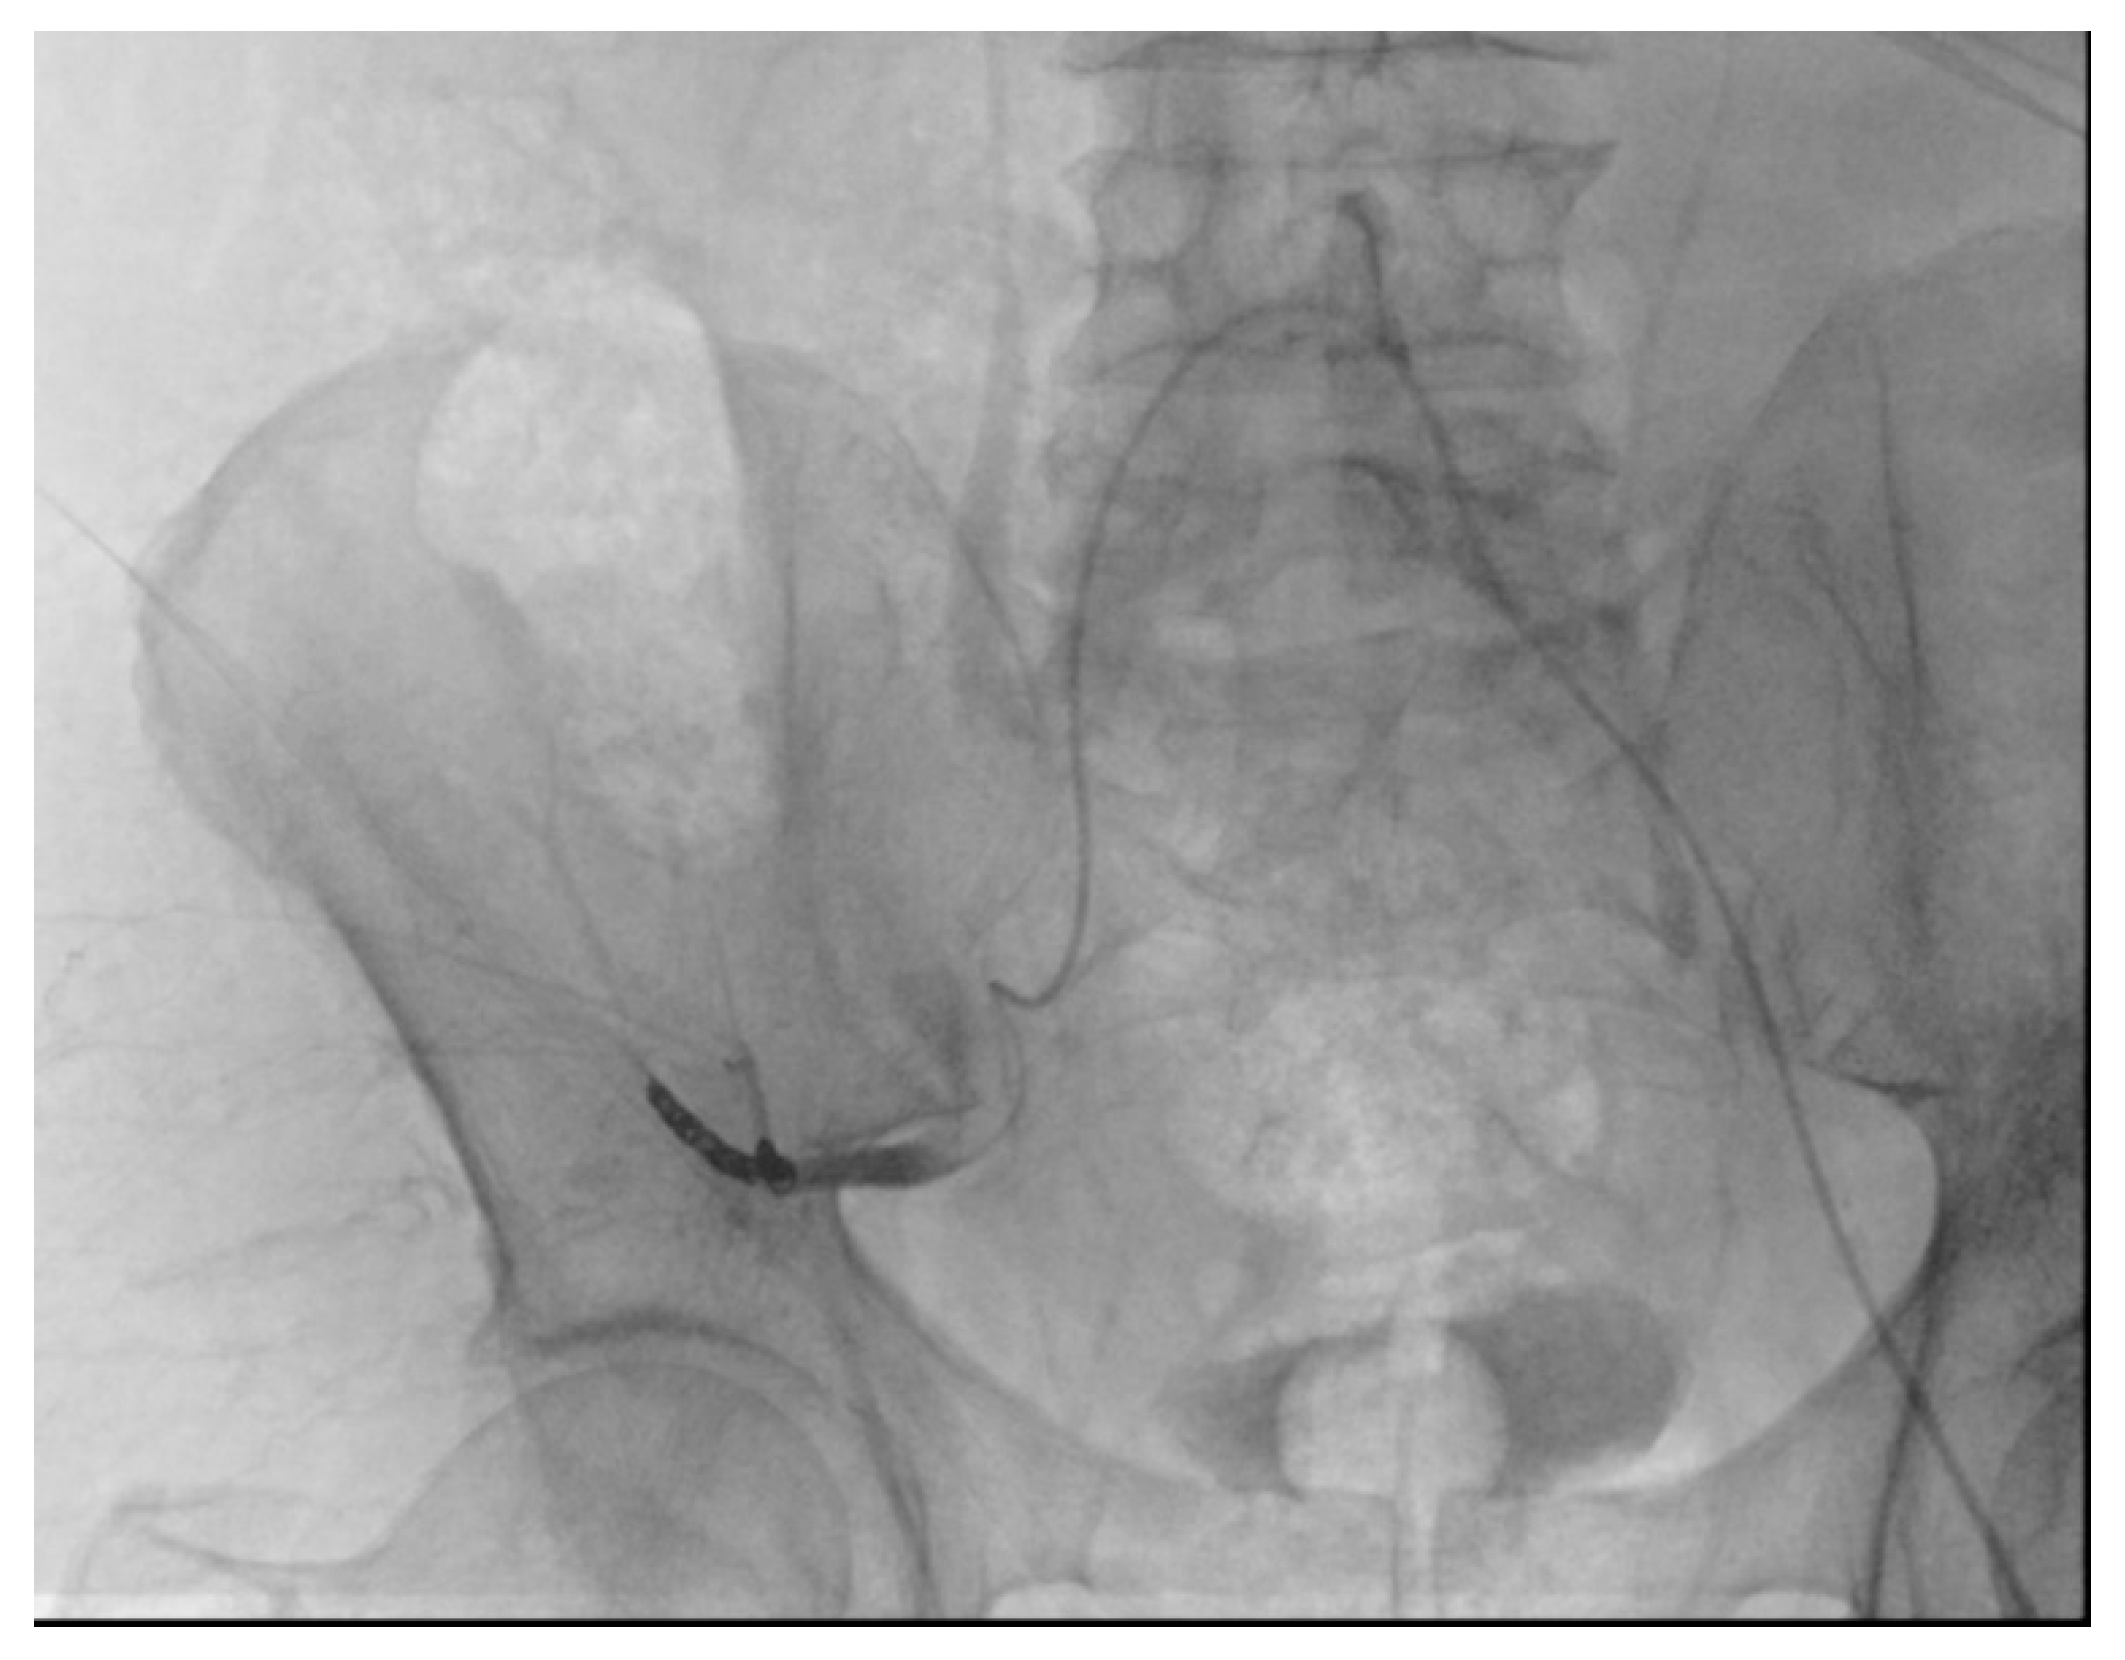

2.5. Procedural Details

- Giurazza, F.; Pane, F.; Roccatagliata, P.; Casciano, E.; Corvino, F.; Festa, P.; Ponticiello, G.; Cappabianca, S.; Romano, L.; Niola, R. Pelvic ring fractures with concomitant large hematomas: Diagnostic investigation with arteriography and eventual embolization in 157 trauma patients, with or without contrast extravasation at emergency CT. Radiol. Med. 2023, 128, 1429–1439. [Google Scholar] [CrossRef] [PubMed]